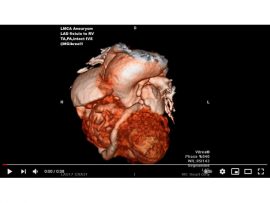

Tricuspid atresia , pulmonary atresia intact IVS Ductus dependent pulmonary circulation LMCA aneurysm Mohamed Gibreel , FEBR (Fellowship of Egyptian Board of Radiology ) Cardiac..